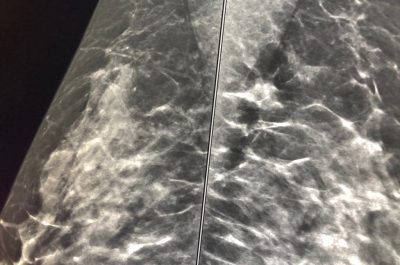

Mammografia 3 D, scoprire i tumori “invisibili”: ecco come funziona e quando è necessaria la tomosintesi